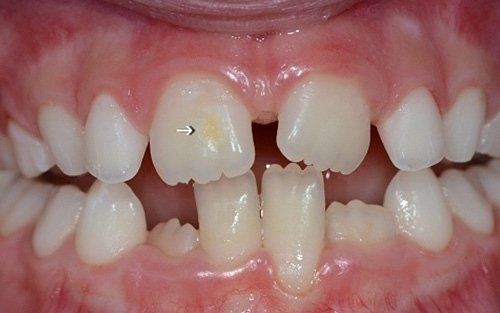

Despite the first signs having been noticed by practitioners at the end of the last century, we can consider the hypomineralisation of molars and incisors (M.I.H. - Molar Incisors Hypomineralisation) as a condition of children in the 2000s. It is characterised by insufficient mineralisation, especially of the first permanent molars, which appear with white-yellowish or brown spots and enamel that is very "porous," lacking the protective shield necessary for the health of these teeth. This leads to a greater tendency for decay, but above all, to structural breakdown of the affected areas under chewing load.